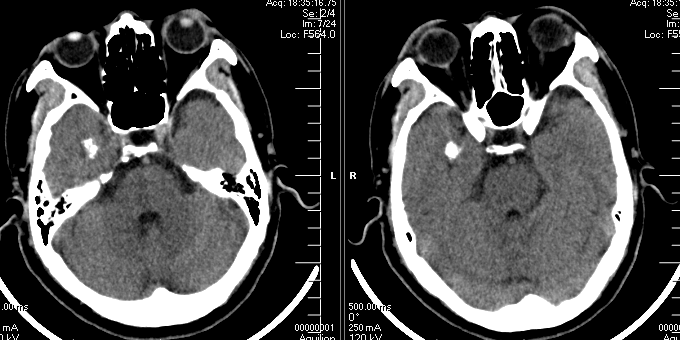

外院头颅CT示右侧颞叶钙化灶,头颅MRI示见右侧颞叶流空信号,考虑动静脉畸形。